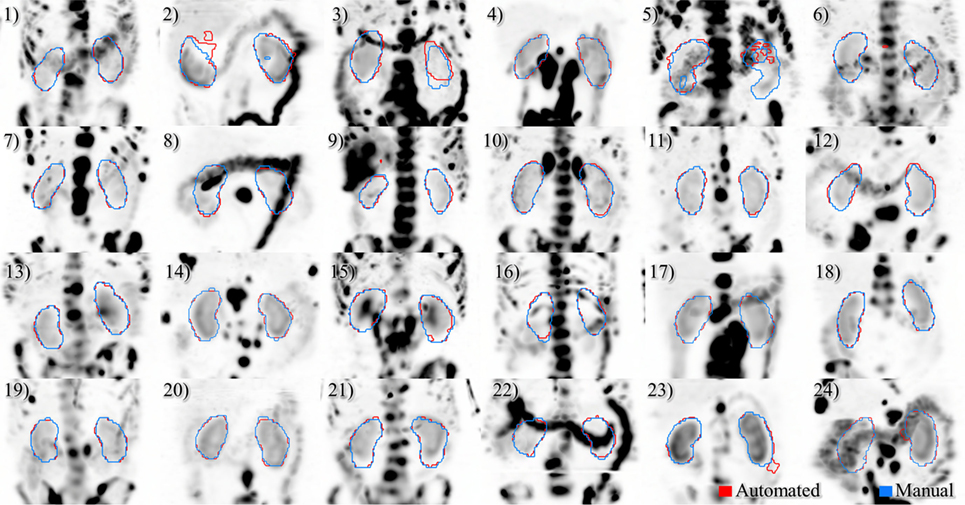

A deep learning segmentation model was trained for detection and accurate delineation of kidneys on non-contrast, low-dose CT scans. A typical result overlaid on fused CT and voxel dose map is given in Figure 4. In more than 80% of cases, margins were in close visual agreement for both kidneys. Visual results of manual and automated contours overlaid with a coronal maximum intensity projection of the voxel dose map for each patient are shown in Figure 5. Even in poorly performing cases, some region of each kidney was detected with the developed registration and CNN method; a volume that was often representative of radionuclide uptake across the organ’s functional structure. When compared to manual segmentation as ground truth, automated contours achieved mean dice scores of 0.91 ± 0.05 and 0.86 ± 0.18 for right and left kidneys, respectively. The mean distance-to-agreement was estimated at 2.0 ± 1.0 and 4.0 ± 7.5 mm; a finer accuracy than the system resolution of typical SPECT imaging device.

Figure 5. Results of automated (red) and manual (blue) segmentation overlaid with maximum intensity projections of voxel dose volumes. Patients 2 and 5 show some disagreement in cystic regions of kidney. In patients 6, 23, and 24 a small volume of bowel is captured by the automated algorithm.

Ignoring the one poorly performing left kidney with dice score of 0.11 and mean distance-to-agreement of 38.3 mm, left kidney accuracy is compared to the right side with a mean dice value of 0.89 ± 0.08 and MDA of 2.5 ± 1.7 mm. It should also be noted that the CNN-defined contours were consistently larger than those drawn manually by a factor of approximately 7%. This systematic effect likely attributed to the upsampling and smoothing of the predicted contours when returning to the native CT resolution and may be corrected by adjusting the prediction threshold to a value slightly above 0.5.

Comparing radiation dose estimates from automated and manually drawn contours, there is no apparent bias using either technique (Figure 6). Across the cohort there was an average difference in dose estimate of 3.0% in the right kidney and −3.6% in the left. SD of the error was ±4.5 and ±5.7%, respectively. If omitting the results for patients with cystic kidneys which would be reviewed and corrected in a clinical workflow—patients #2, 3, and 5 in Figure 5—the discrepancy in dose estimates between manual and automated methods is less than 2% for both kidneys. Based on t-test of null hypothesis, no difference between dose estimates between groups was detected (p = 0.03 and p = 0.01, right and left). Results of contour accuracy and renal radiation dose for each patient are reported in Table S1 in Supplementary Material.

Three of the patients in the 177Lu-PSMA therapy cohort displayed highly cystic kidneys; to a degree that was not observed in the training patients (Figure 7). In these cases, the mean dice score was dramatically lower at 0.66. No systematic increase or decrease in estimated dose was shown (−2.70%) indicating that often the CNN-contoured region was representative of the mean uptake in the manually delineated kidney. In another three patients, a small, detached section (<10 cc) of bowel was included one of the contours. In none of the cases did error manifest in an appreciable effect on estimated renal dose. If frequently noted, small non-contiguous labels could be detected and removed as a post-processing step. Only one patient with structurally normal kidneys showed poor performance with the segmentation algorithm omitting approximately one-third of the left kidney volume (dice = 0.67); an error which coincided with a region of CT streak artifact.